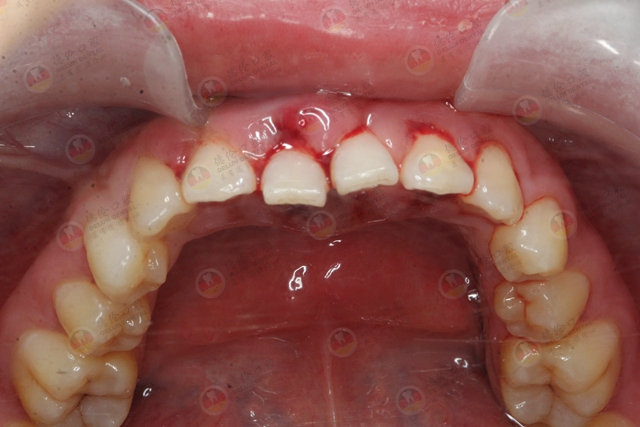

洗牙会造成牙龈出血吗?

需要明确的是:造成牙龈出血的主要原因是牙结石刺激牙龈发炎,引发牙龈出血,包括洗牙过程出血,而不是洗牙导致出血。

为了避免牙结石堆积、牙龈出血,定期洗牙就好了。洗完牙后,牙龈就会慢慢恢复健康,以后刷牙就不会出血了~